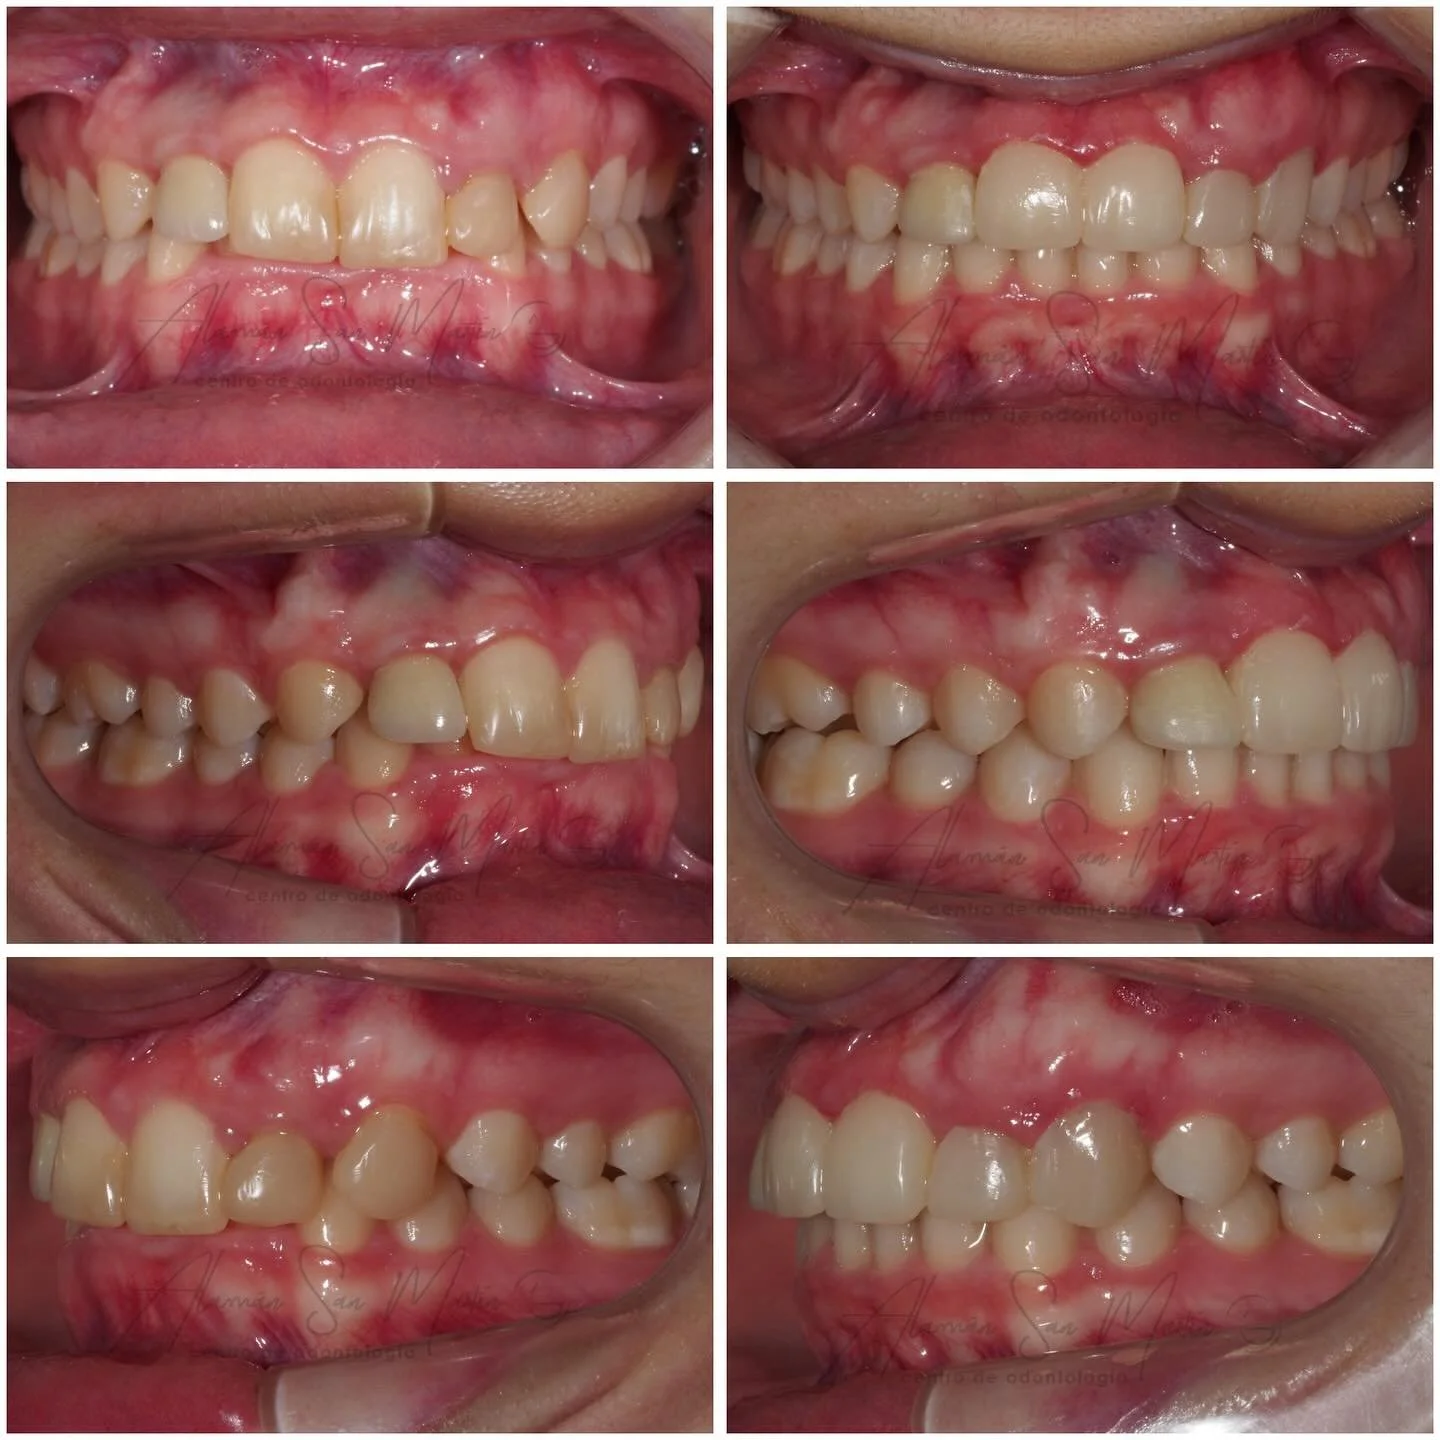

En la Clínica Alamán San Martín todos los tratamientos de Ortodoncia los realiza un Especialista Universitario en Ortodoncia, siempre tras un estudio diagnóstico en profundidad con la exploración clínica y valoración de todos los registros necesarios según la complejidad de cada paciente.

Actualmente la Ortodoncia se realiza a cualquier edad para mejorar la salud bucal, la función masticatoria y la estética, al conseguir un buen alineamiento de los dientes y una relación ósea intermaxilar adecuada con una oclusión normal, por lo que recomendamos hacer una revisión de ortodoncia por lo menos desde los 6 años de edad si no se detecta nada antes.

En Clínica Alamán San Martín ofrecemos diversos tratamientos de ortodoncia como: Ortodoncia infantil y adultos, Ortodoncia Estética, Ortodoncia Transparente con Alineadores, y Ortodoncia quirúrgica para Cirugía ortognática.